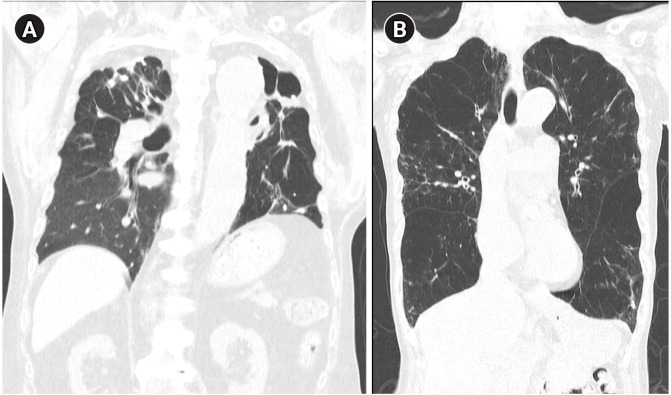

慢性阻塞性肺疾病(COPD)是呼吸道疾病和死亡的主要原因,通常与吸烟有关。然而,越来越多的证据表明,既往结核病感染也是COPD的一个关键危险因素。本文综述了结核病-慢性阻塞性肺病的流行病学意义、发病机制、临床特点和目前的治疗方法。结核病相关慢性阻塞性肺疾病(TB-COPD)的特征是持续的炎症反应、免疫途径改变和广泛的结构性肺损伤,表现为空化、纤维化和气道重塑。多项流行病学研究表明,有结核病病史的人患慢性阻塞性肺病的可能性明显更高,并出现更糟糕的结果,如呼吸困难加剧和病情频繁恶化。主要的致病机制包括基质金属蛋白酶活性升高和中性粒细胞驱动的过度炎症,导致肺泡破坏、纤维化瘢痕形成和支气管扩张的发展。治疗一般遵循当前COPD指南,提倡使用长效支气管扩张剂和选择性应用吸入皮质类固醇。研究表明,茚达特罗可显著改善肺功能和呼吸系统症状,而长效毒蕈碱拮抗剂已显示出生存益处。

Chronic obstructive pulmonary disease (COPD) is a leading cause of respiratory morbidity and mortality, most often linked to smoking. However, growing evidence indicates that previous tuberculosis (TB) infection is also a critical risk factor for COPD. This review aimed at providing a comprehensive perspective on TB-COPD, covering its epidemiologic significance, pathogenesis, clinical characteristics, and current management approaches. Tuberculosis-associated chronic obstructive pulmonary disease (TB-COPD) is characterized by persistent inflammatory responses, altered immune pathways, and extensive structural lung damage-manifested as cavitation, fibrosis, and airway remodeling. Multiple epidemiologic studies have shown that individuals with a history of TB have a significantly higher likelihood of developing COPD and experiencing worse outcomes, such as increased breathlessness and frequent exacerbations. Key pathogenic mechanisms include elevated matrix metalloproteinase activity and excessive neutrophil-driven inflammation, which lead to alveolar destruction, fibrotic scarring, and the development of bronchiectasis. Treatment generally follows current COPD guidelines, advocating the use of long-acting bronchodilators and the selective application of inhaled corticosteroids. Studies have demonstrated that indacaterol significantly improves lung function and respiratory symptoms, while long-acting muscarinic antagonists have shown survival benefits.